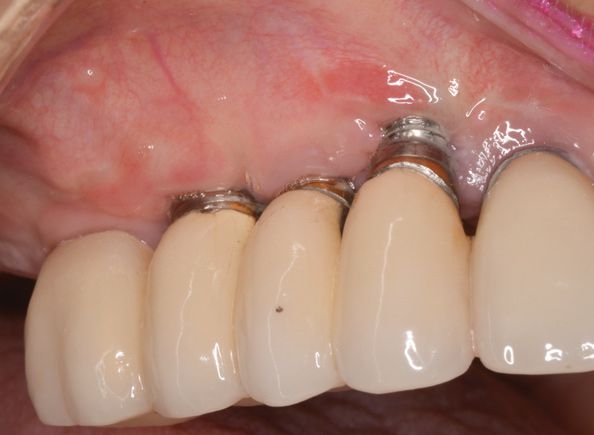

Периимплантит – одонтогенная инфекция, сопровождающаяся поражением мягких и костных тканей в области дентального имплантата и резорбцией кости. Клиника периимплантита характеризуется болью в области имплантата, гиперемией и отеком десны, образованием десневого кармана, кровотечением или гноетечением, подвижностью конструкции. Периимплантит диагностируется в ходе стоматологического осмотра с учетом жалоб, клинической и рентгенологической картины. Полноценное лечение периимплантита проводится поэтапно: 1 (консервативный) – удаление зубных отложений и устранение воспаления; 2 (хирургический) - очистка поверхности имплантата и костная пластика. В некоторых случаях показано удаление имплантата с последующей реимплантацией после необходимого лечения.

Периимплантит – воспаление тканей вокруг остеоинтегрированного имплантата, приводящее к прогрессирующей убыли опорной кости. По данным клинических исследований, при использовании различных современных имплантационных систем периимплантит развивается в 12-43% случаев. Перимплантит является одной из частых причин отторжения дентального имплантата. От периимплантита следует отличать мукозит - воспаление прилегающего к имплантату участка слизистой без признаков убыли костной ткани.

Мукозит, или периимплантное воспаление клинически проявляется набуханием и кровоточивостью десны, гиперплазией периимплантатной манжетки. Резорбции костной ткани при мукозите не происходит. В отличие от поверхностного воспаления, при периимплантите отмечается прогрессирующая убыль костной ткани. Больные жалуются на боль в области установленного имплантата, отек, гиперемию и кровоточивость периимплантатной десны; образование десневых карманов и свищей, из которых может выделяться гнойное содержимое.

При объективном обследовании пациентов с периимплантитом определяется гиперемия и отек мягких тканей. При зондировании десны отмечается кровоточивость; при пальпации периимплантатного кармана из него может выделяться гнойный экссудат. Имплантат подвижен; на соседних зубах и ортопедической конструкции выявляется скопление мягкого налета. Оценка состояния периимплантатной десны производится с помощью стоматоскопии.

При осмотре и зондировании врач может выявить:

- мягкий микробный налёт на имплантате, пищевые остатки и зубной камень;

- кровоточивость десны вокруг имплантата;

- незначительную болезненность и отёчность прилегающей десны;

- неподвижность имплантата;

- отсутствие кармана вокруг имплантата.